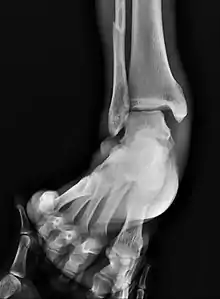

On X-rays, there can be a fracture of the medial malleolus, the lateral malleolus, and/or of the anterior/posterior margin of the distal tibia. The posterior margin (known as the posterior malleolus) is much more frequently injured than the anterior aspect of the distal tibia. If both the lateral and medial malleoli are broken, this is called a bimalleolar fracture (some of them are called Pott's fractures). If the posterior malleolus is also fractured, this is called a trimalleolar fracture.

A triplane fracture of the ankle as seen on plain X-ray